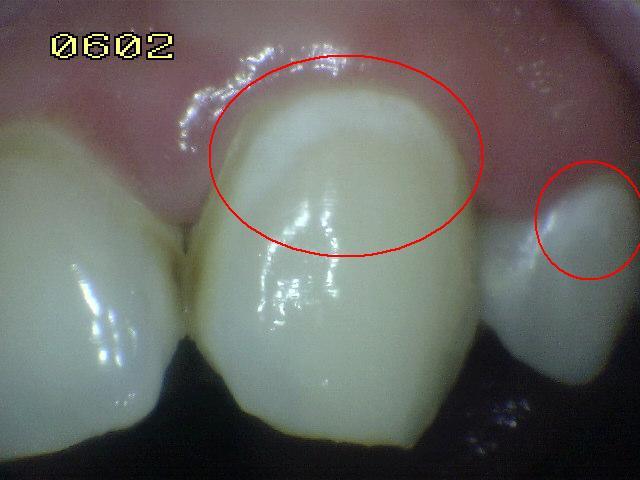

Icdas 1

HALLAZGO CLINICO:

mancha blanca o

cafe vista en

superficie seca

sobre esmalte

restringida solo a

fosas y fisuras

CARIES ACTIVA:

esmalte opaco con

perdida de brillo;

generalmente

cubierta de placa.

CARIES INACTIVA:

esmalte brillante y

duro, no hay

perdida

clinicamente

detectable de la

sustancia

Caries no

cavitacional

que afecta

solo el

esmalte

TRATAMIENTO:

educación en

higiene oral y

aplicación de

barniz de fluor.